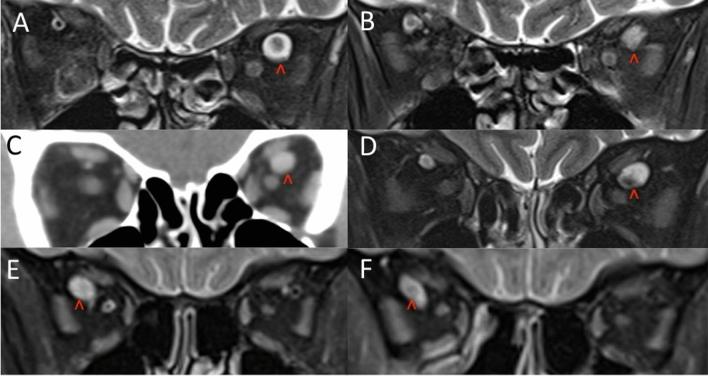

Retrospective review of patients who had dilated SOVs with a diameter of ≥ 5.0 mm. Patients with a dilated SOV secondary to orbital, cavernous sinus or neurological disease were excluded. Patient demographics, past medical history, and SOV diameters on initial and follow up scans were collected. The maximum diameter of the SOV was taken perpendicular to the long axis of the SOV.

Nine cases were identified. Patients ranged in age from 58 to 89 years and six out of nine were female. The dilated SOV involved both eyes in two cases, left eye in five cases and right eye in two cases. Three patients had dilated SOV likely secondary to raised venous pressures from decompensated right heart failure (n = 1), pericardial effusion (n = 1) and left ventricle dysfunction secondary to a myocardial infarction (n = 1). Five patients had a significant history of previous ischaemic heart or peripheral vascular disease. Two patients had risk factors for venous clotting disease whilst one patient had a history of giant cell arteritis and vertebral artery dissection.